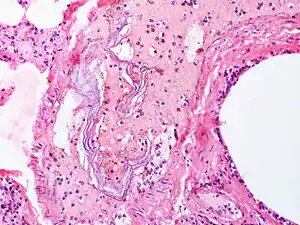

| Skin cells are present in the blood vessels of this case of amniotic fluid embolism. | |

AFE is diagnosed when other causes have been excluded. Fetal squamous cells or other fetal tissues, including meconium, have been found in the maternal circulation after the event. Diagnosis is also based upon symptoms.[6]